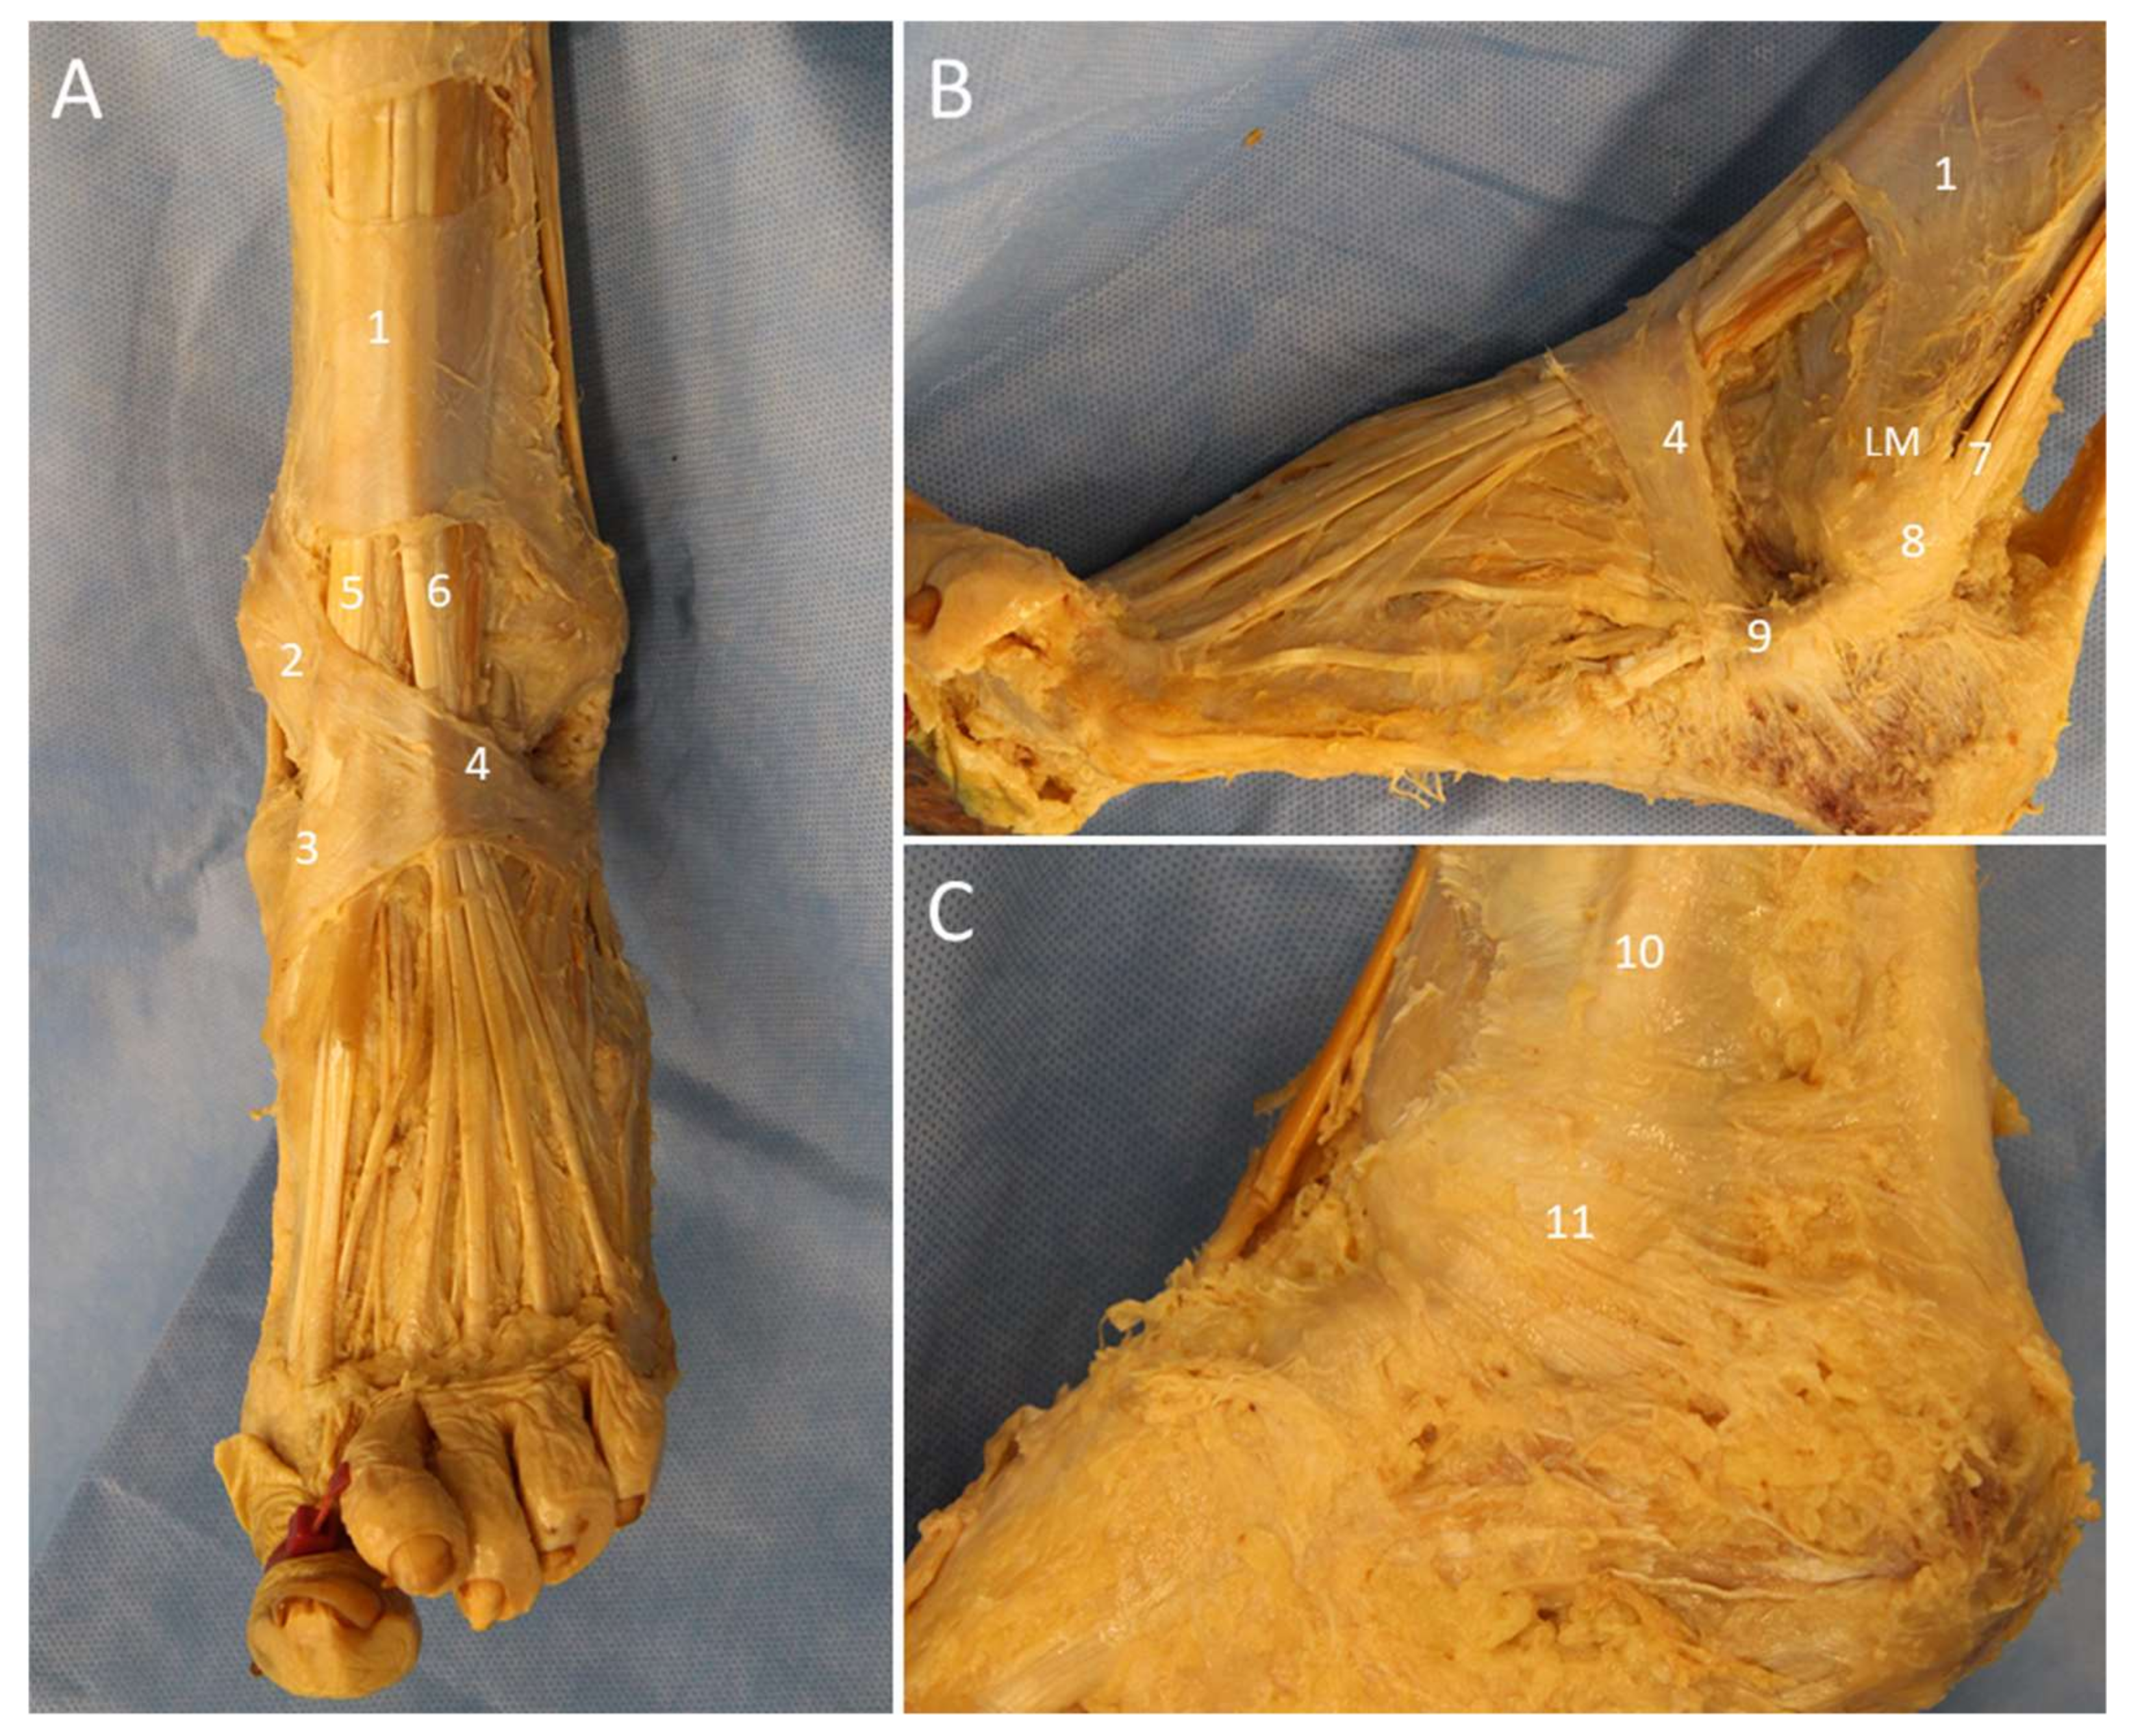

3. Retinacula

3.1. Anatomy

3.2. Scanning Technique

3.3. Clinical Relevance